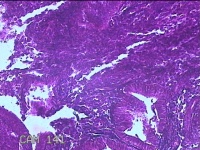

性别

男

年龄

57岁

临床诊断

慢性胃炎;胃肠功能紊乱;肠道菌群失调;结肠息肉

一般病史

上腹部胀痛1月余。

标本名称

直肠粘膜

大体所见

直肠可见多个息肉样隆起,部分表面粗糙。